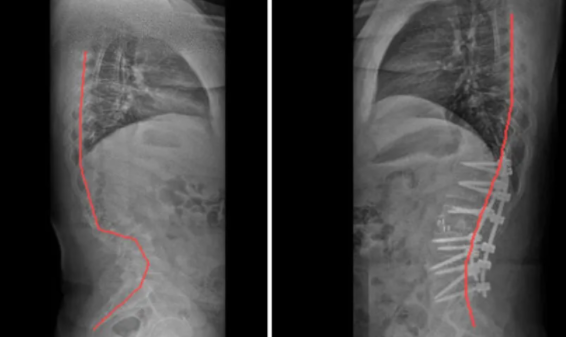

半椎体畸形脊柱侧弯术前(左)、术后(右)